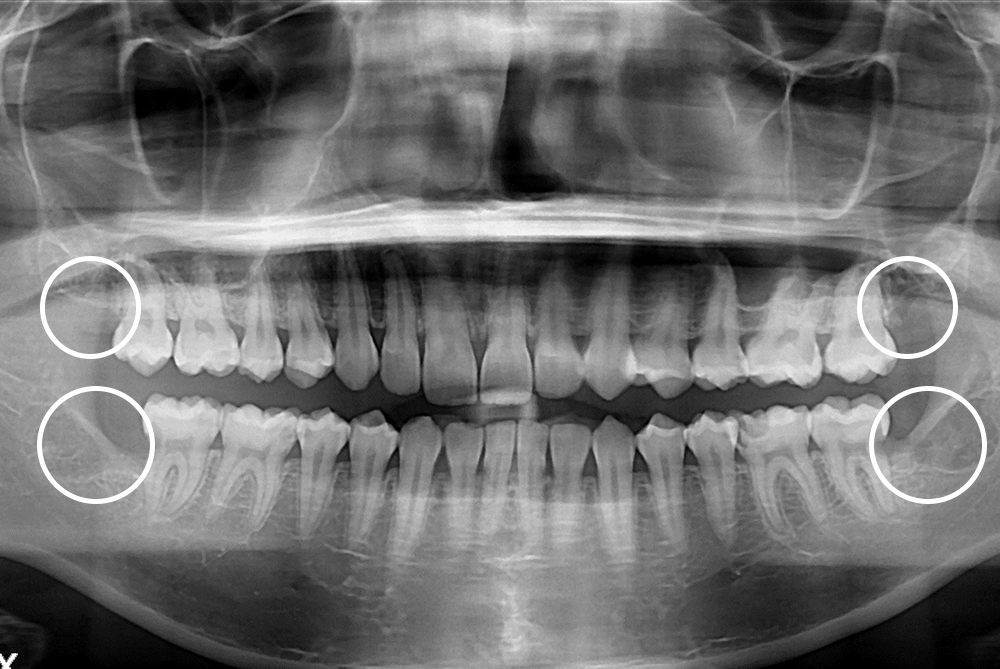

[사랑니] 매복 사랑니 발치

치료후 : 2018-10-19